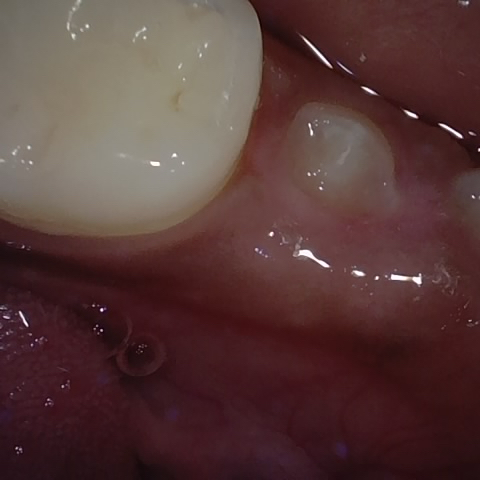

NHD25470

Annotated as "Good"